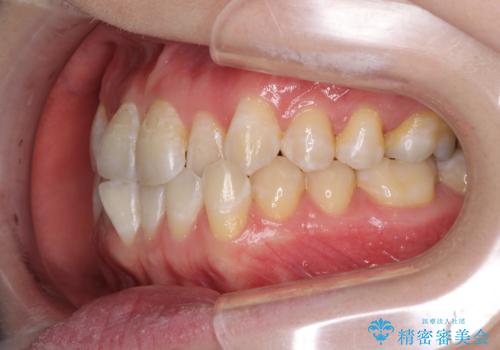

前歯のデコボコを治したい インビザラインによる矯正治療

- 前歯のデコボコを治したいとのことで来院された患者様です。

上下顎ともに歯列全体の後方移動とIPR(歯と歯の間を削る)によってデコボコが解消するように設計し、インビザラインにより治療を行うこととしました。

1日22時間の装着時間をほとんど達成することができず、治療には当初予定の2倍以上の期間を要することとなりました。